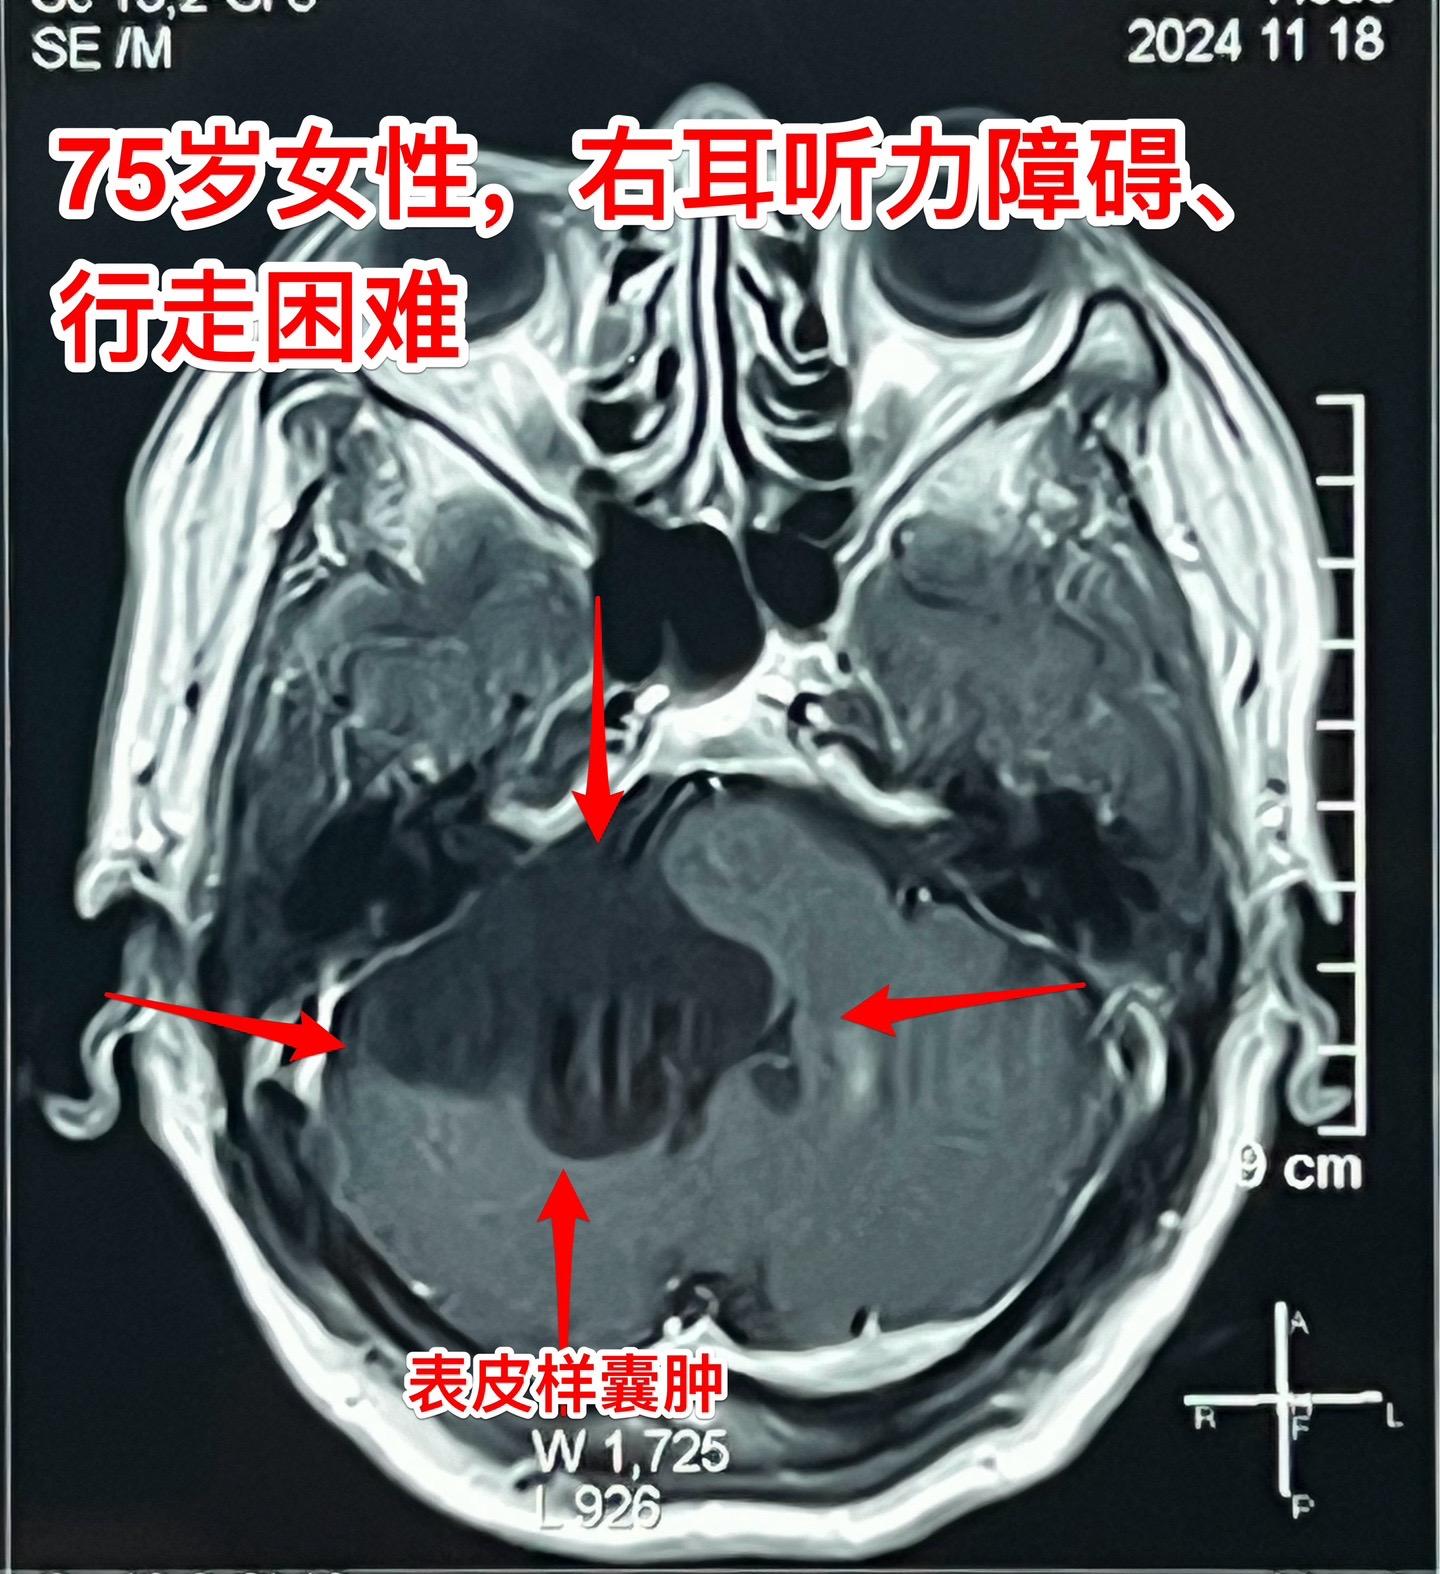

75岁的老奶奶决定接受开颅手术了!75岁的辽宁省海城老奶奶在5年前就曾发现脑部长了一个可疑肿瘤(怀疑为表皮样囊肿或者胆脂瘤),右耳听力下降。当时在沈阳就医,医生建议作手术,但是考虑到病人已经70岁高龄了,手术风险很大,当时老人和家属就决定不作手术。 在五年时间内老人的病情在慢慢加重,逐渐出现行走困难,生活质量越来越差。儿女孝顺,都想方设法地希望能够改善老人的生活质量! 老人的女婿有个表哥,张先生,患颅咽管瘤,曾经在2016年因颅咽管瘤复发了在我这里作了手术。手术后8年了,